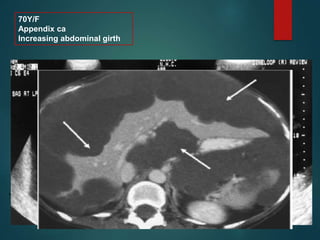

70Y/F

Appendix ca

Increasing abdominal girth

• Pronounced scalloping

• Calcifications.

• #10 1. It is a clinical syndrome, characterized by recurrent and recalcitrant voluminous mucinous ascites due to surface growth on the peritoneum without significant invasion of underlying tissues. 2.A distinctive CT appearance is produced by pseudomyxoma peritonei in which the peritoneal surfaces become diffusely involved with large amounts of mucinous material. Although there is continued debate regarding the site of origin of pseudomyxoma peritonei, clinicopathologic studies suggest that the vast majority of cases arise from primary mucinous adenomas of the appendix, with the ovaries being secondarily involved (79,231,248,326). Although a more benign form (disseminated peritoneal adenomucinosis) and a more malignant form (peritoneal mucinous carcinomatosis) of the disease have been described, the imaging findings of the two forms overlap (22). CT findings include low-attenuation masses with discrete walls or diffuse intraperitoneal low-attenuation material that may contain septations and often causes scalloping of the hepatic, splenic and mesenteric margins (58,177,206,263,287,308,324) (Figs. 16-87, 16-88, 16-89). Calcifications are not uncommon in patients with large volume disease (177), particularly after chemotherapy (176,287). If the walls of the cystic masses are thin, the CT appearance may be similar to that produced by loculated ascites. Scalloping of the liver, spleen and mesenteric margins by extrinsic pressure of the gelatinous masses and failure of the bowel loops to “float” to the anterior abdominal wall may be useful in differentiating pseudomyxoma peritonei from ascites (263). P.1142

• #11 Pseudomyxoma peritonei in a 70-year-old woman who complained of increasing abdominal girth. Longitudinal (a) and transverse (b) sonograms of the abdomen show complex, hypoechoic ascites that contains nonmobile echoes and centrally displaced small bowel that has a starburst appearance